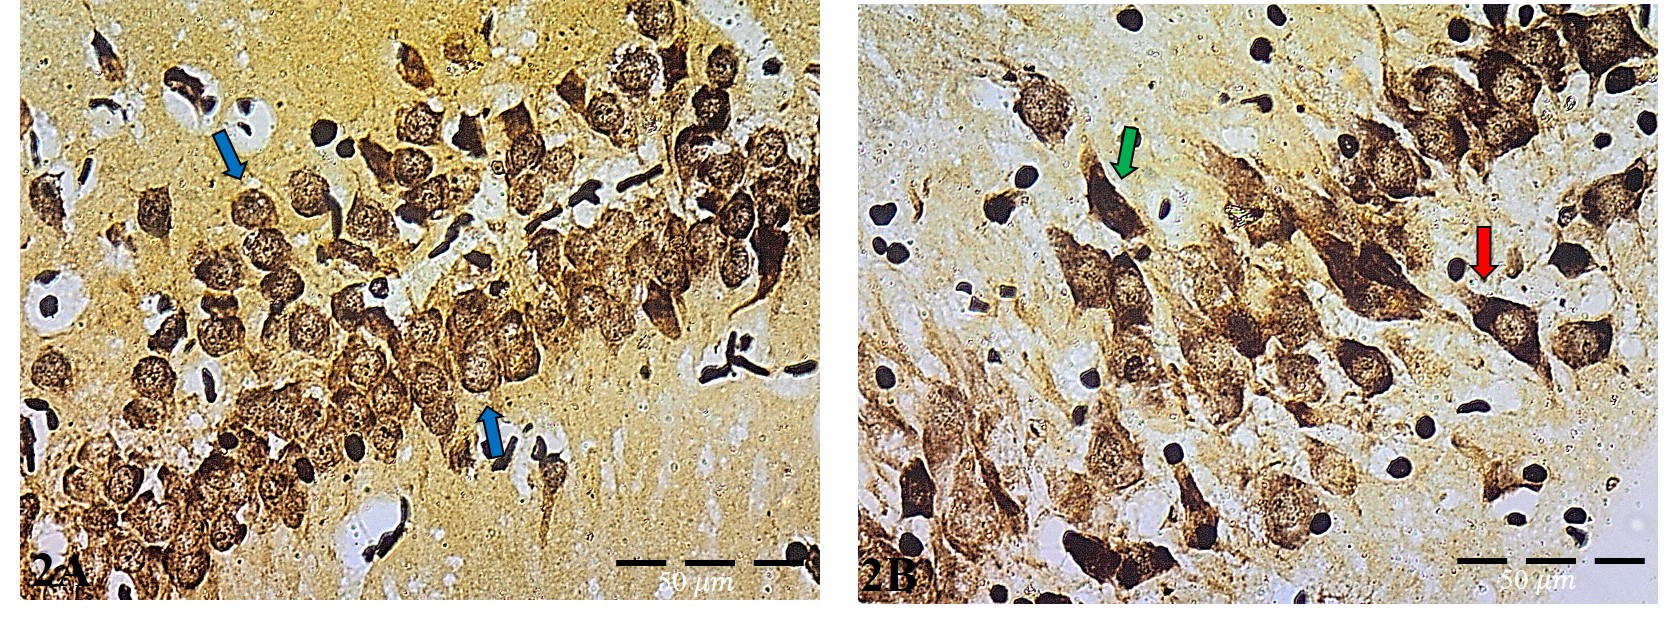

• Histological results of Gallyas-Braak silver stain:

• Control group

The examination of CA3 area showed the normal morphological structure of pyramidal cells with observation of their arrangement, each pyramidal cell appeared normal with a single, rounded central large, vesicular nucleus with prominent nucleoli (Figure 2A).

• The Wi Fi group:

In this group, the pyramidal cells lost their normal architecture and normal arrangements. The pyramidal cells appeared darkly stained and destructed cells with shrunken cell bodies, pyknotic nuclei and surrounded by dark stained processing (Figure 2B).

Gallyas-Braak silver stain using, provided us by a clear vision about the effect of EMR on hippocampal different regions as increase the degeneration rate of hippocampal neurons specially the pyramidal neurons as previously described by (El-Kafoury, Hamam et al. 2019). In the Wi-Fi group there was apparent increase in number of cells containing neurofibrillary tangles in their cell bodies as an indicator for cell degeneration appeared by silver stain. These results came with agreement of (Marson, Lasaponara et al. 2021) study.